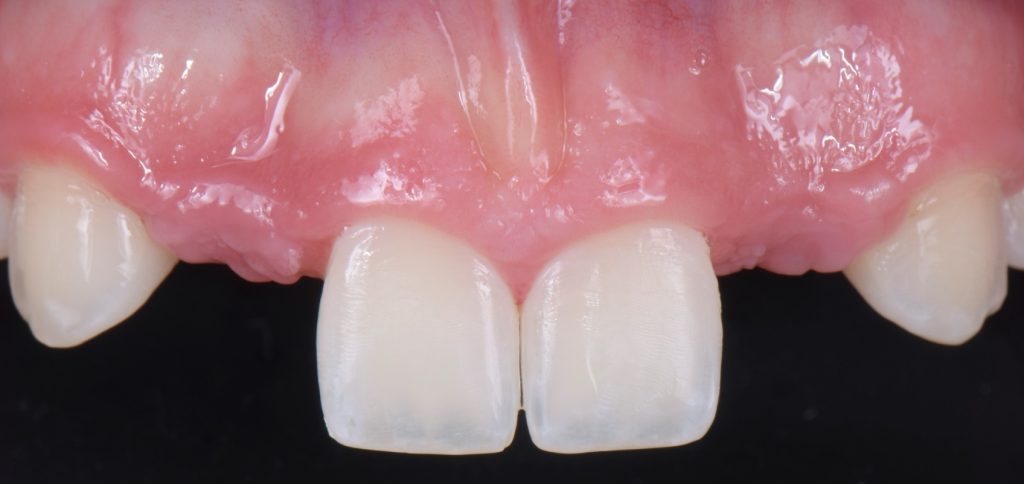

Solution #2: Resin-Bonded Fixed Dental Prostheses (RBFDP)

RBFDP is a proven solution for congenitally missing lateral incisors (Figs. 2-12). Although it is considered an interim restoration, the literature provides substantial evidence supporting its long-term potential. However, the clinical performance of an RBFDP is significantly superior to that of a bilateral retainer, and the dissimilar mobility of the abutment teeth explains this.

When placing an RBFDP from a central incisor to a canine, each abutment wants to move under occlusal load, but because of the position each tooth occupies in the arch, loading occurs in different vectors, therefore, leading to debonding of the retainer of the abutment tooth with the least mobility. When considering which one of the adjacent teeth will work best as the abutment, the clinician needs to evaluate:

From an occlusal standpoint, patients with shallow overbites or a large amount of overjet make better candidates for RBFDP, and the pontics should be avoided in all lateral excursions, including crossover.

Space requirements and connector dimensions depend on material selection. Utilizing zirconia has been proven to be more predictable over time, and recommended connector dimensions are:

- 3.0 mm in height

- 2.0 mm in width

- The retainer wing thickness is 0.7 mm

The amount of tooth reduction is based on available interocclusal space, and often, there is enough space requiring minimal preparation. The key is to stay in enamel. It is also advisable to stay 2.0 mm away from the incisal edge so that the zirconia retainer does not affect the translucency of the natural tooth.

If the patient has a deep overbite, proclined teeth, or mobile abutment teeth, an RBFPD may not be the best treatment option. This is why they are often used as a long-term provisional until the patient is old enough to have an implant placed.